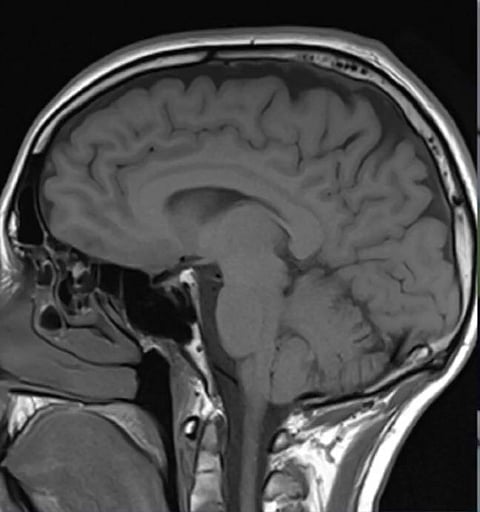

The researchers also analysed the brains of three patients who succumbed to Covid-19.

SARS-CoV-2 was detected in the cortical neurons of one of these patients, and the infected brain regions were associated with ischemic infarcts in which decreased blood supply causes localized tissue damage and cell death. Microinfarcts were detected in the brain autopsy of all three patients.